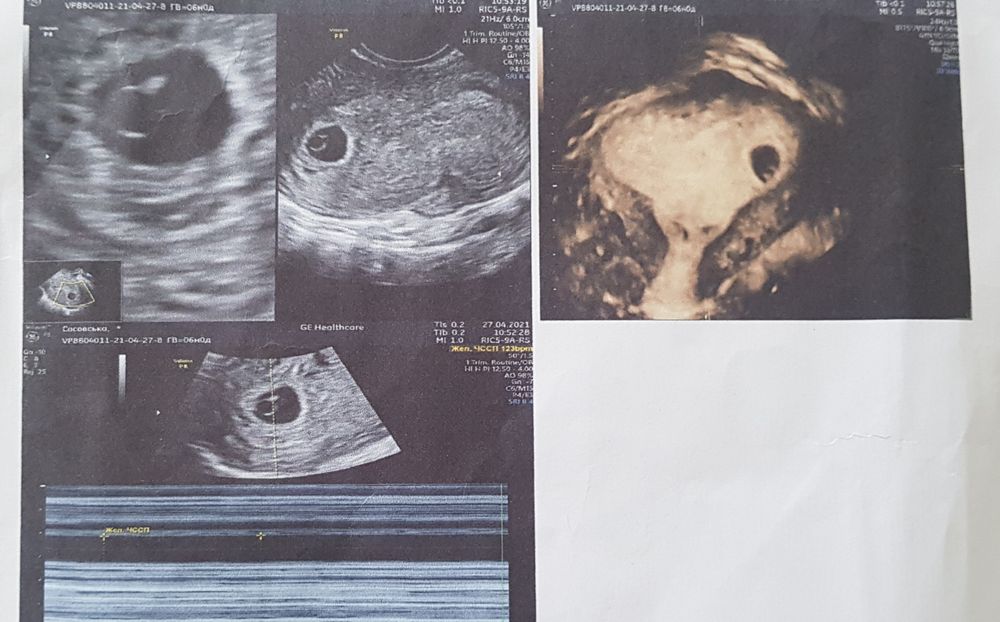

УЗИ делала вагинально оба раза. Первое фото 6 недель по М, а второе 8 недель по М. Итак, у кого какие предложения?!😅😅